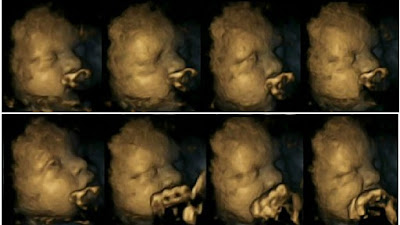

สำนักข่าวต่างประเทศ ได้รายงานผลการวิจัยของ Dr Nadja Reissland จากมหาวิทยาลัยเดอรัม (Durham University) เกี่ยวกับผลกระทบของการสูบบุหรี่ในขณะตั้งครรภ์ พร้อมกับเผย ภาพอัลตราซาวน์ 4 มิติ หรือ 4D ที่แสดงถึงภาพของทารกในครรภ์ที่มีลักษณะการเจริญเติบโต รวมไปถึงการหายใจที่ผิดปกติ และพบว่ามีจำนวนหลายรายถึงขั้นเสียชีวิตภายในครรภ์ไปเลยก็มี

ทั้งนี้นักวิจัยมีความเชื่อว่า หากมีการเปิดเผยข้อมูลเกี่ยวกับผลกระทบจากการสูบบุหรี่หรืออยู่ใกล้ควันบุหรี่ในขณะกำลังตั้งครรภ์ อาจช่วยสร้างแรงบันดาลให้ให้หญิงสาวเหล่านี้ได้ตัดสินใจเลิกสูบบุหรี่อย่างจริงจังเสียที

ภาพ 4D ของลูกน้อยที่แม่สูบบุหรี่ตอนตั้งครรภ์